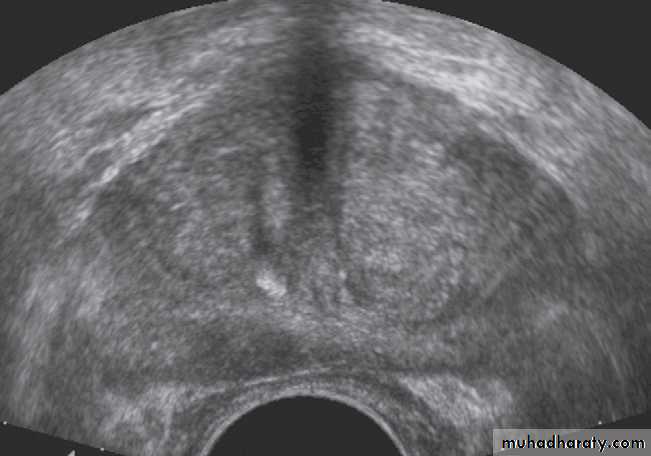

Prostatic enlargement is very common in elderly men. It is usually due to benign hypertrophy but may be due to carcinoma.Prostatic ultrasound uses a

transducer designed to be

introduced into the rectum.

Transrectal ultrasound (TRUS)

can show the overall size of the

prostate and can diagnose

relatively small masses within

its substance .